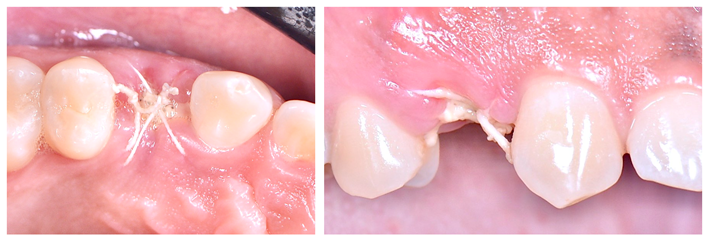

Finalizada a compactação do enxerto ósseo no sítio alveolar (Figura 7), o alvéolo foi selado com a membrana (Figura 7) e realizou-se a sutura com o fio Cytoplast, da Implacil De Bortoli (Figura 9), que é monofilamentar e feito em PTFE (Politetrafluoretileno). Essas características resultam em menor agregação bacteriana e em certa elasticidade do fio, o que reduz a chance de deiscência da sutura, uma vez que ele acompanha o deslocamento do tecido durante a inflamação e aumento de volume. Quatro semanas após a cirurgia, a sutura e a membrana foram removidas (Figuras 10 e 11). Como a membrana não é absorvível, ela deve ser removida entre 21 e 28 dias após a sua instalação. Após o período de 90 dias, realizou-se uma nova tomografia para se avaliar o correto posicionamento tridimensional do implante e a osteointegração (Figura 14).